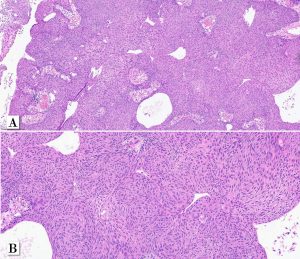

A male patient in his early 70s underwent surgical removal a single pedunculated 3 cm polypoid tumor in the bladder mucosa at the left lateral wall.

Papillary urothelial carcinoma, noninvasive, whorled subtype

One rare morphologic subtype of in noninvasive papillary urothelial carcinoma has been described as a whorled pattern. Patriarca et al. 2014 described a series of 12 patients: all noninvasive and most of them 11/12 classified as low-grade. One patient had a tumor with mixed grade (5% of the tumor at other areas. Whorled pattern shows concentrically organized cell structures, without morphological evidence of keratinization, similar to the whorling structures of transitional meningioma.

In that series, none of the cases experienced T1 stage progression and two recurrences occurred. One of the recurrent tumors was the one harboring small focus of high-grade tumor inside the primary lesion. Interestingly, the recurrent cases maintained the same whorling pattern in the second transurethral resection specimens. Therefore, although limited data on follow up is available, clinical behavior seems to be similar to low-grade noninvasive papillary urothelial carcinoma (Patriarca et al. 2014). Awareness of this morphologic subtype is important to avoid misclassification of other epithelial lesions which may show squamous or squamoid morphology.